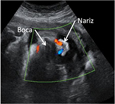

Ver la cara de un feto en rotación es posible gracias a esta ecografía en 4D. El ultrasonido es capaz de ofrecer un fiel reflejo de los rasgos faciales del bebé, que ya se encuentra en su tercer trimestre de gestación.

Ecografía 4D de la cara de un bebé en el tercer trimestre de embarazo

Vemos un primer plano en rotación del rostro de un feto en el tercer trimestre de embarazo. Los rasgos faciales del niño se perfilan con gran claridad en este examen ecográfico.